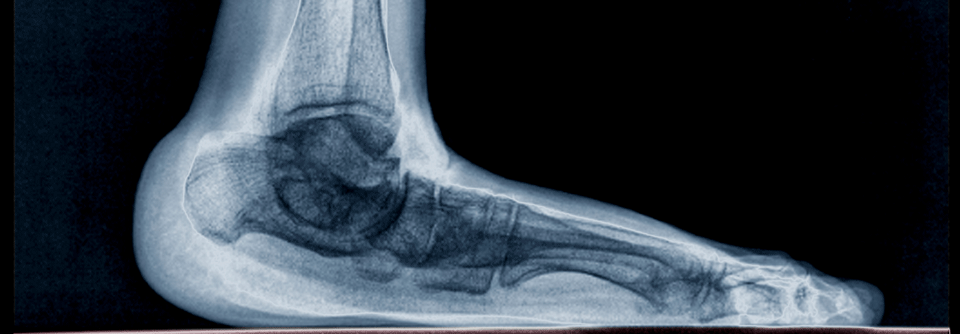

Pes planus

Gesunde Plattfüße in Ruhe lassen

Jahrzehntelang wurden Plattfüße überbewertet und übertherapiert. Denn für die Hypothese, dass ein Plattfuß die Verletzungsgefahr erhöht, gibt es…

Orthopädie